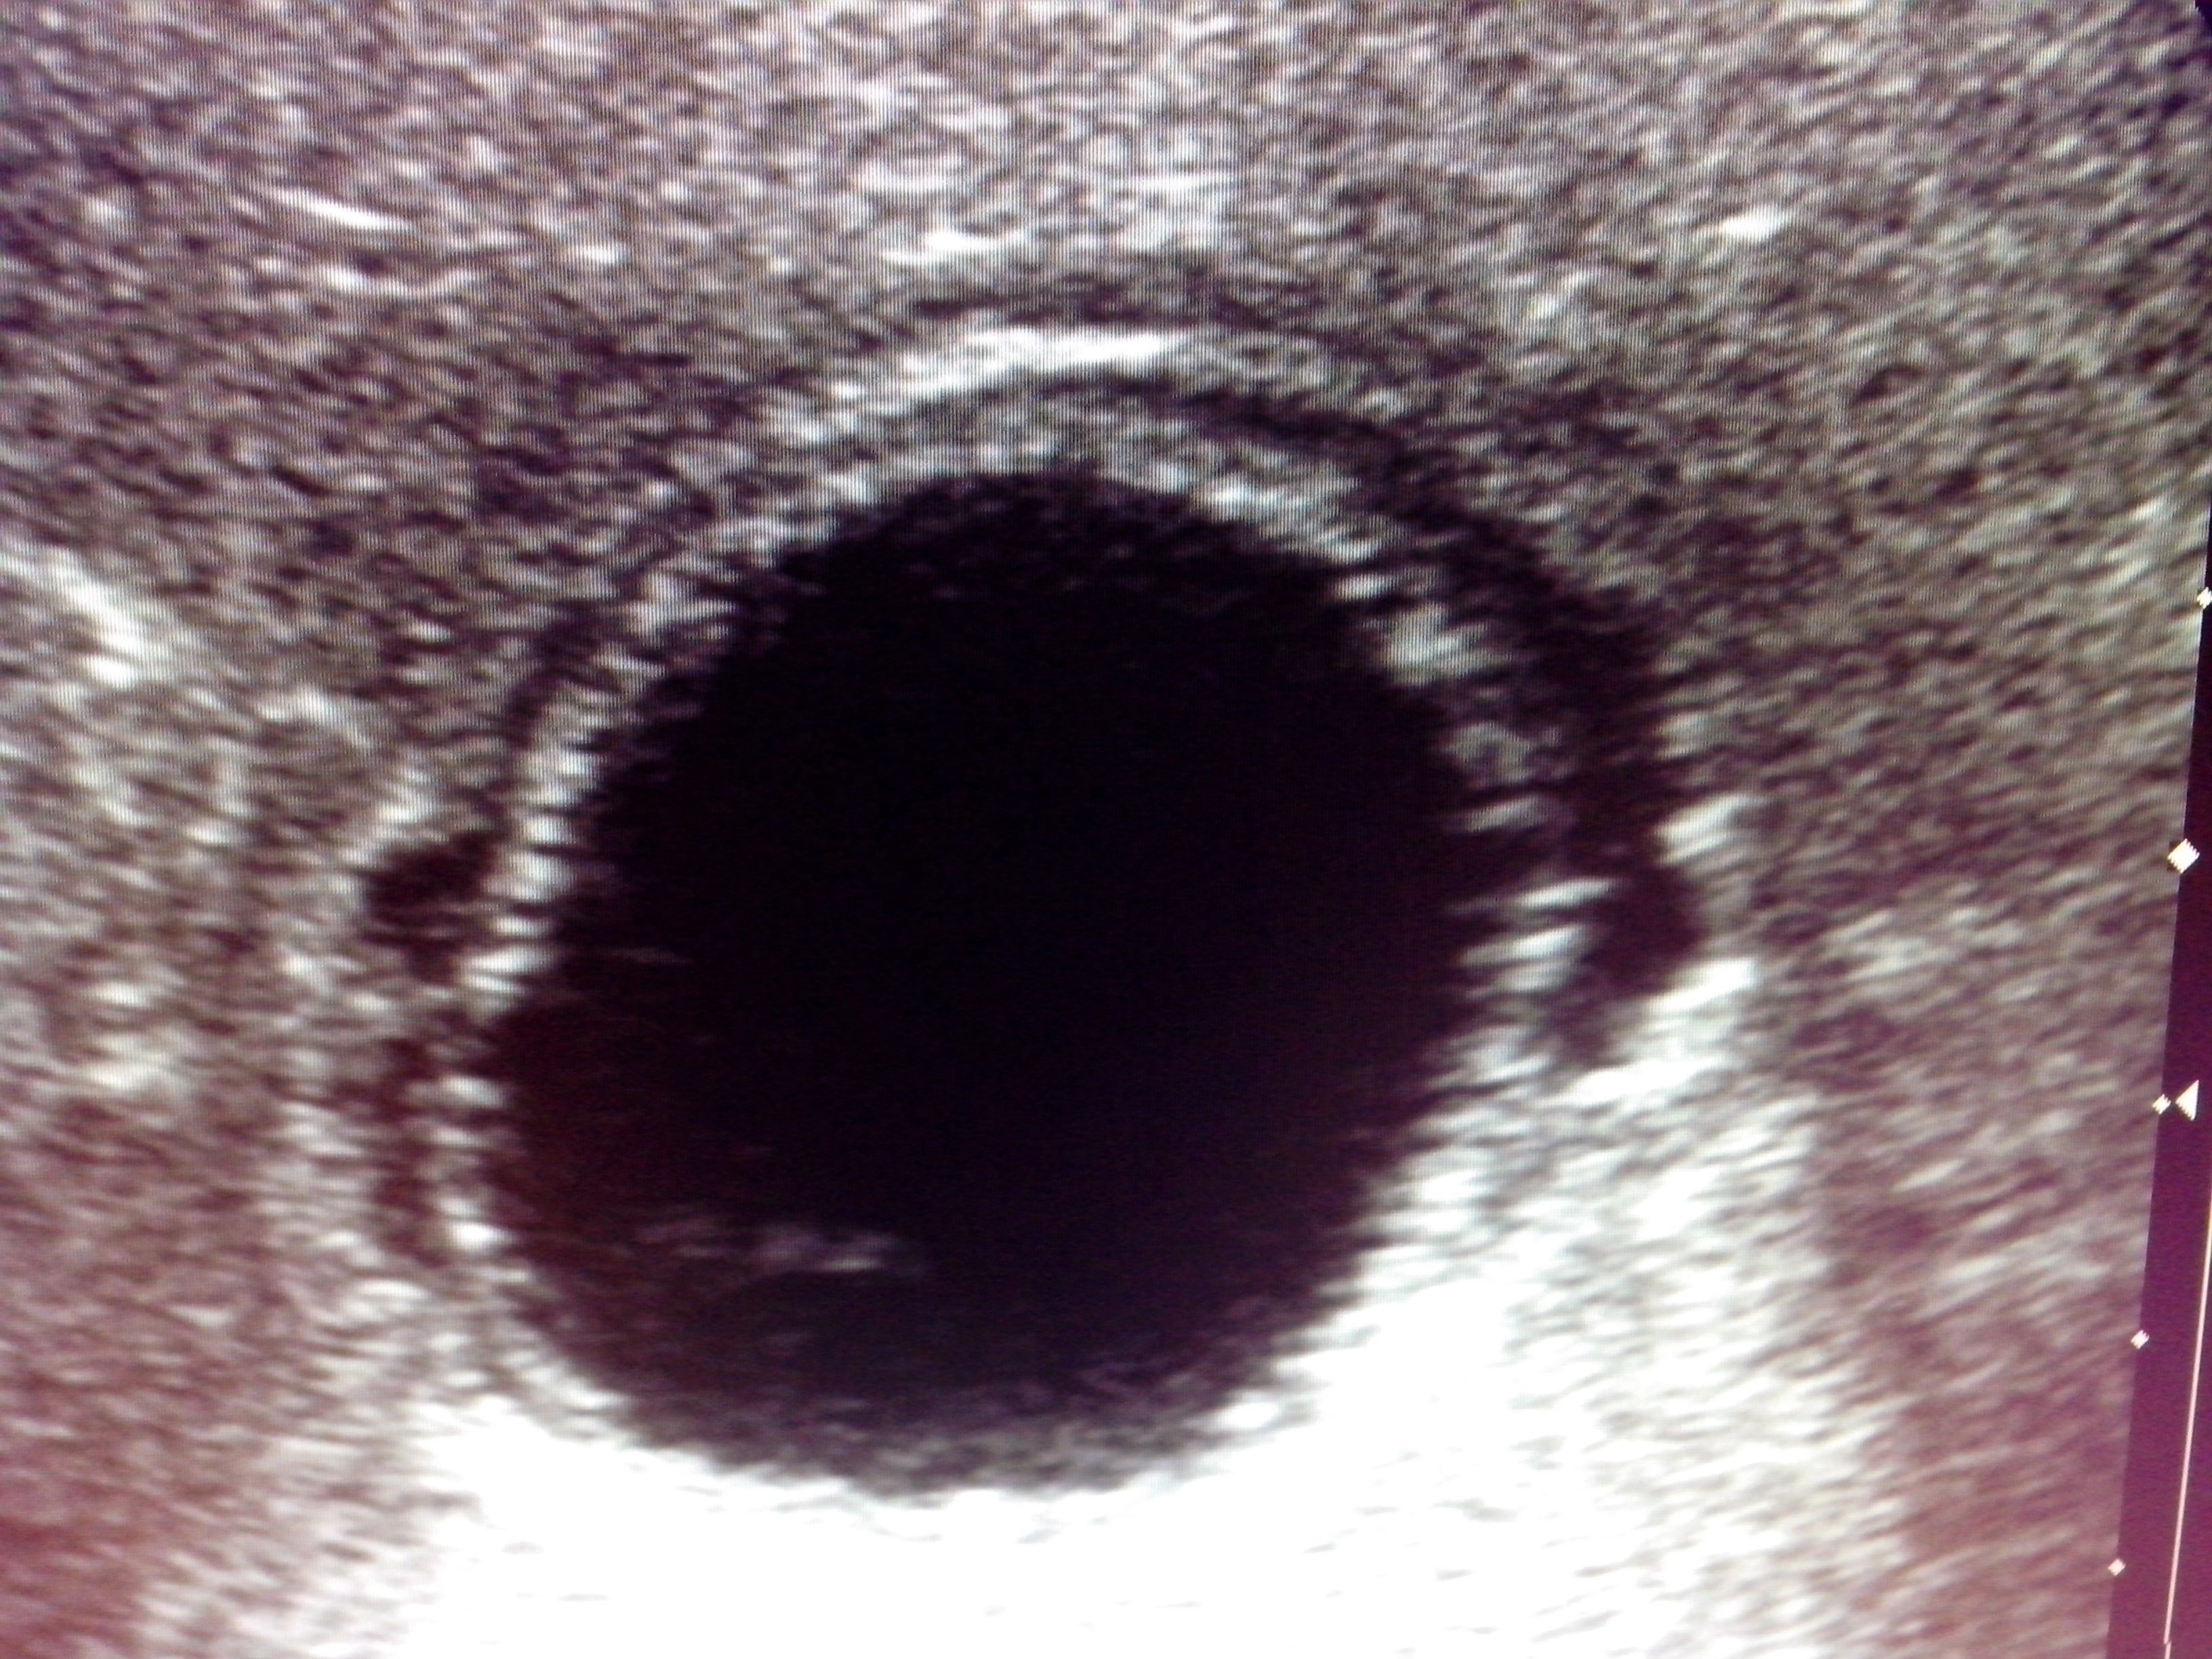

При УЗИ выявлены признаки отслоения внутренней оболочки в одной из кист правой доли:

| |